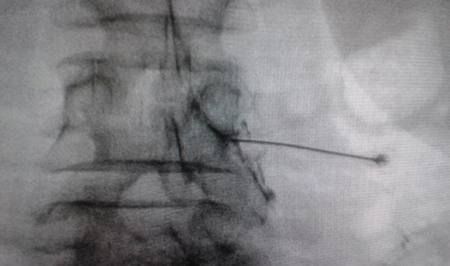

Figura 1

Figura 2